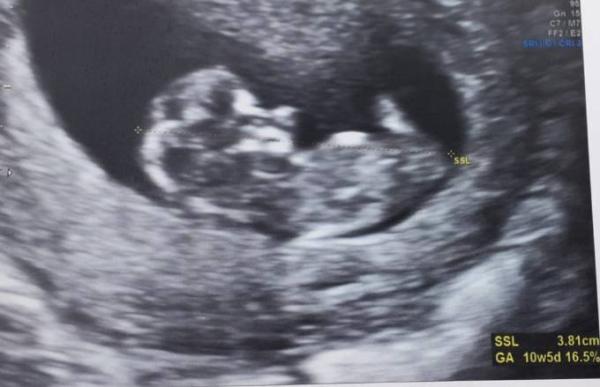

Hallo zusammen, Ich trau mich jetzt auch zu euch zu kommen Ich hatte heute meinen zweiten FA Termin, und ich war ganz schön aufgeregt...beim letzten Termin vor vier Wochen (in der 7.SSW) wurde ich 1 Woche zurück datiert weil der Embryo laut FA viel zu klein war (2,3 mm) Ich hatte solche Angst das es wieder eine Fehlgeburt wird (MA im Nov'20 9./10. Ssw) Aber zum Glück war heute alles super Das kleine Würmchen hat voll aufgeholt und hat beim Ultraschall richtig gezappelt und das Herzchen hat fest geschlagen :-) ganze 3.8 cm ist es jetzt groß und hat den Rückstand voll aufgeholt. Bin jetzt 10+5 , ET 14.1.22 Ich bin so glücklich Liebe Grüße an alle und eine schöne Schwangerschaft

Bild zu Ich bin auch dabei - Forum für Januar - Mamis

Herzliche willkommen. Ein sehr schönes Ultraschall Bild hast du da Wünsche dir eine gute gesunde Schwangerschaft. LG